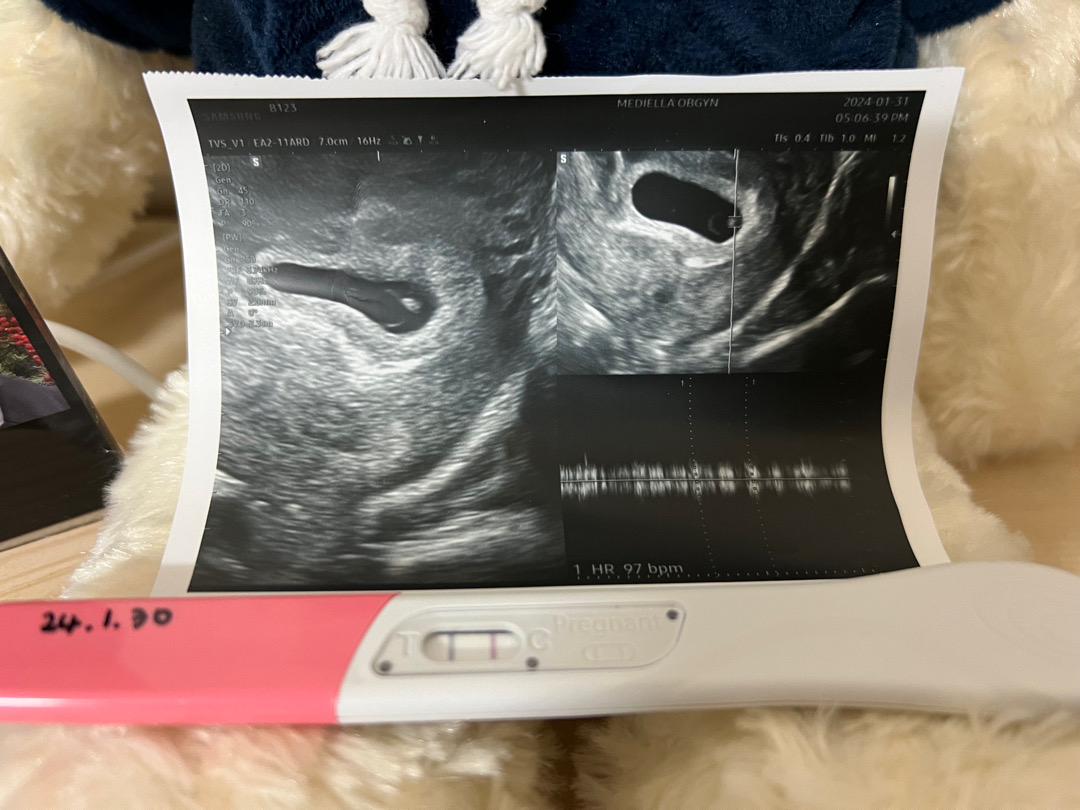

ㅈㅅ한데 초음파사진 왼쪽은 무슨사진이에요?기계처럼보여서용

안녕하세요~ 이번달 중순부터 속이 울렁거리고 생리도 안해서 테스트기와 병원에서 확인해보니 아기를 가졌더라구효! 제 아가는 아직 2mm이래요😍 질문은 아기가 5주차쯤 되었다고하는데 그것때문에 입덧으로 속울렁거림과 속이 답답한 증상이 있는거같고 평소보다 몸에 힘이 없어지고 잠이 더더더 많아진건 저 뿐만인가요?? 원래 이런거죠..?

왼쪽에 기계처럼 보이는게 어떤걸까요..?? 초음파사진에있는 애기 심장 박동수 말씀하시는걸까요??